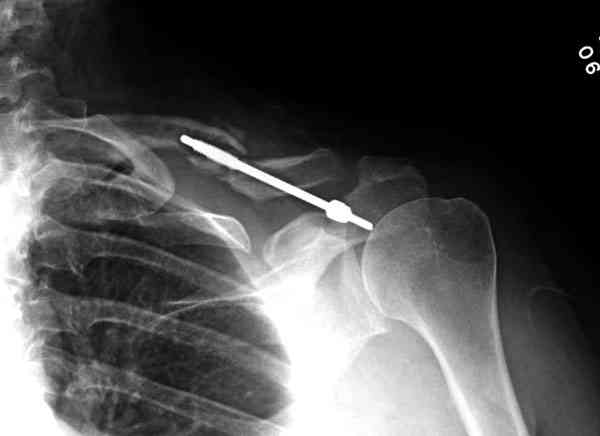

Недавно разбирали случай ложного сустава.

45 летная женщина после автоаварии, алкоголь 163 и 20 летним стажем курения.

Консервативное лечение, через 8 мес. операция Rockwood pin с костной пластикой в нашем городе другим врачом. После 8 недели падение, гвоздь удален оперирующим хирургом, больная направлена к нам. Фиксация реконструктивной пластиной с трикортикальным графтом, добавлен BMP-2. Для стабилизации фиксацию провели через акромион.

Вот уже два месяца больная также продолжает жаловаться на боли, буквально на днях удалили акромиальную часть пластины с специальной пилой с алмазным покрытием для медицинского металла. До сих пор судьба ложного сустава неизвестна....